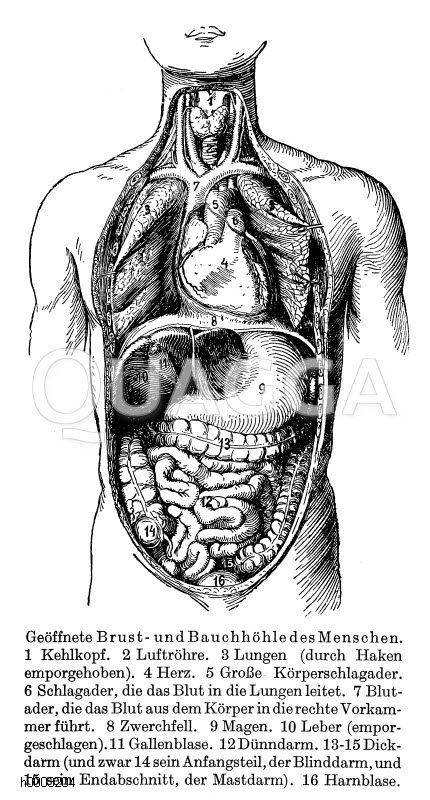

Brust- und Bauchhöhle des Menschen: Zeichnung/Illustration/Holzstich – – human thoracic and abdominal cavity – Cavités thoraciques et abdominales de l’homme

Anatomy; Human; organ, anatomie ; être humain ; organe